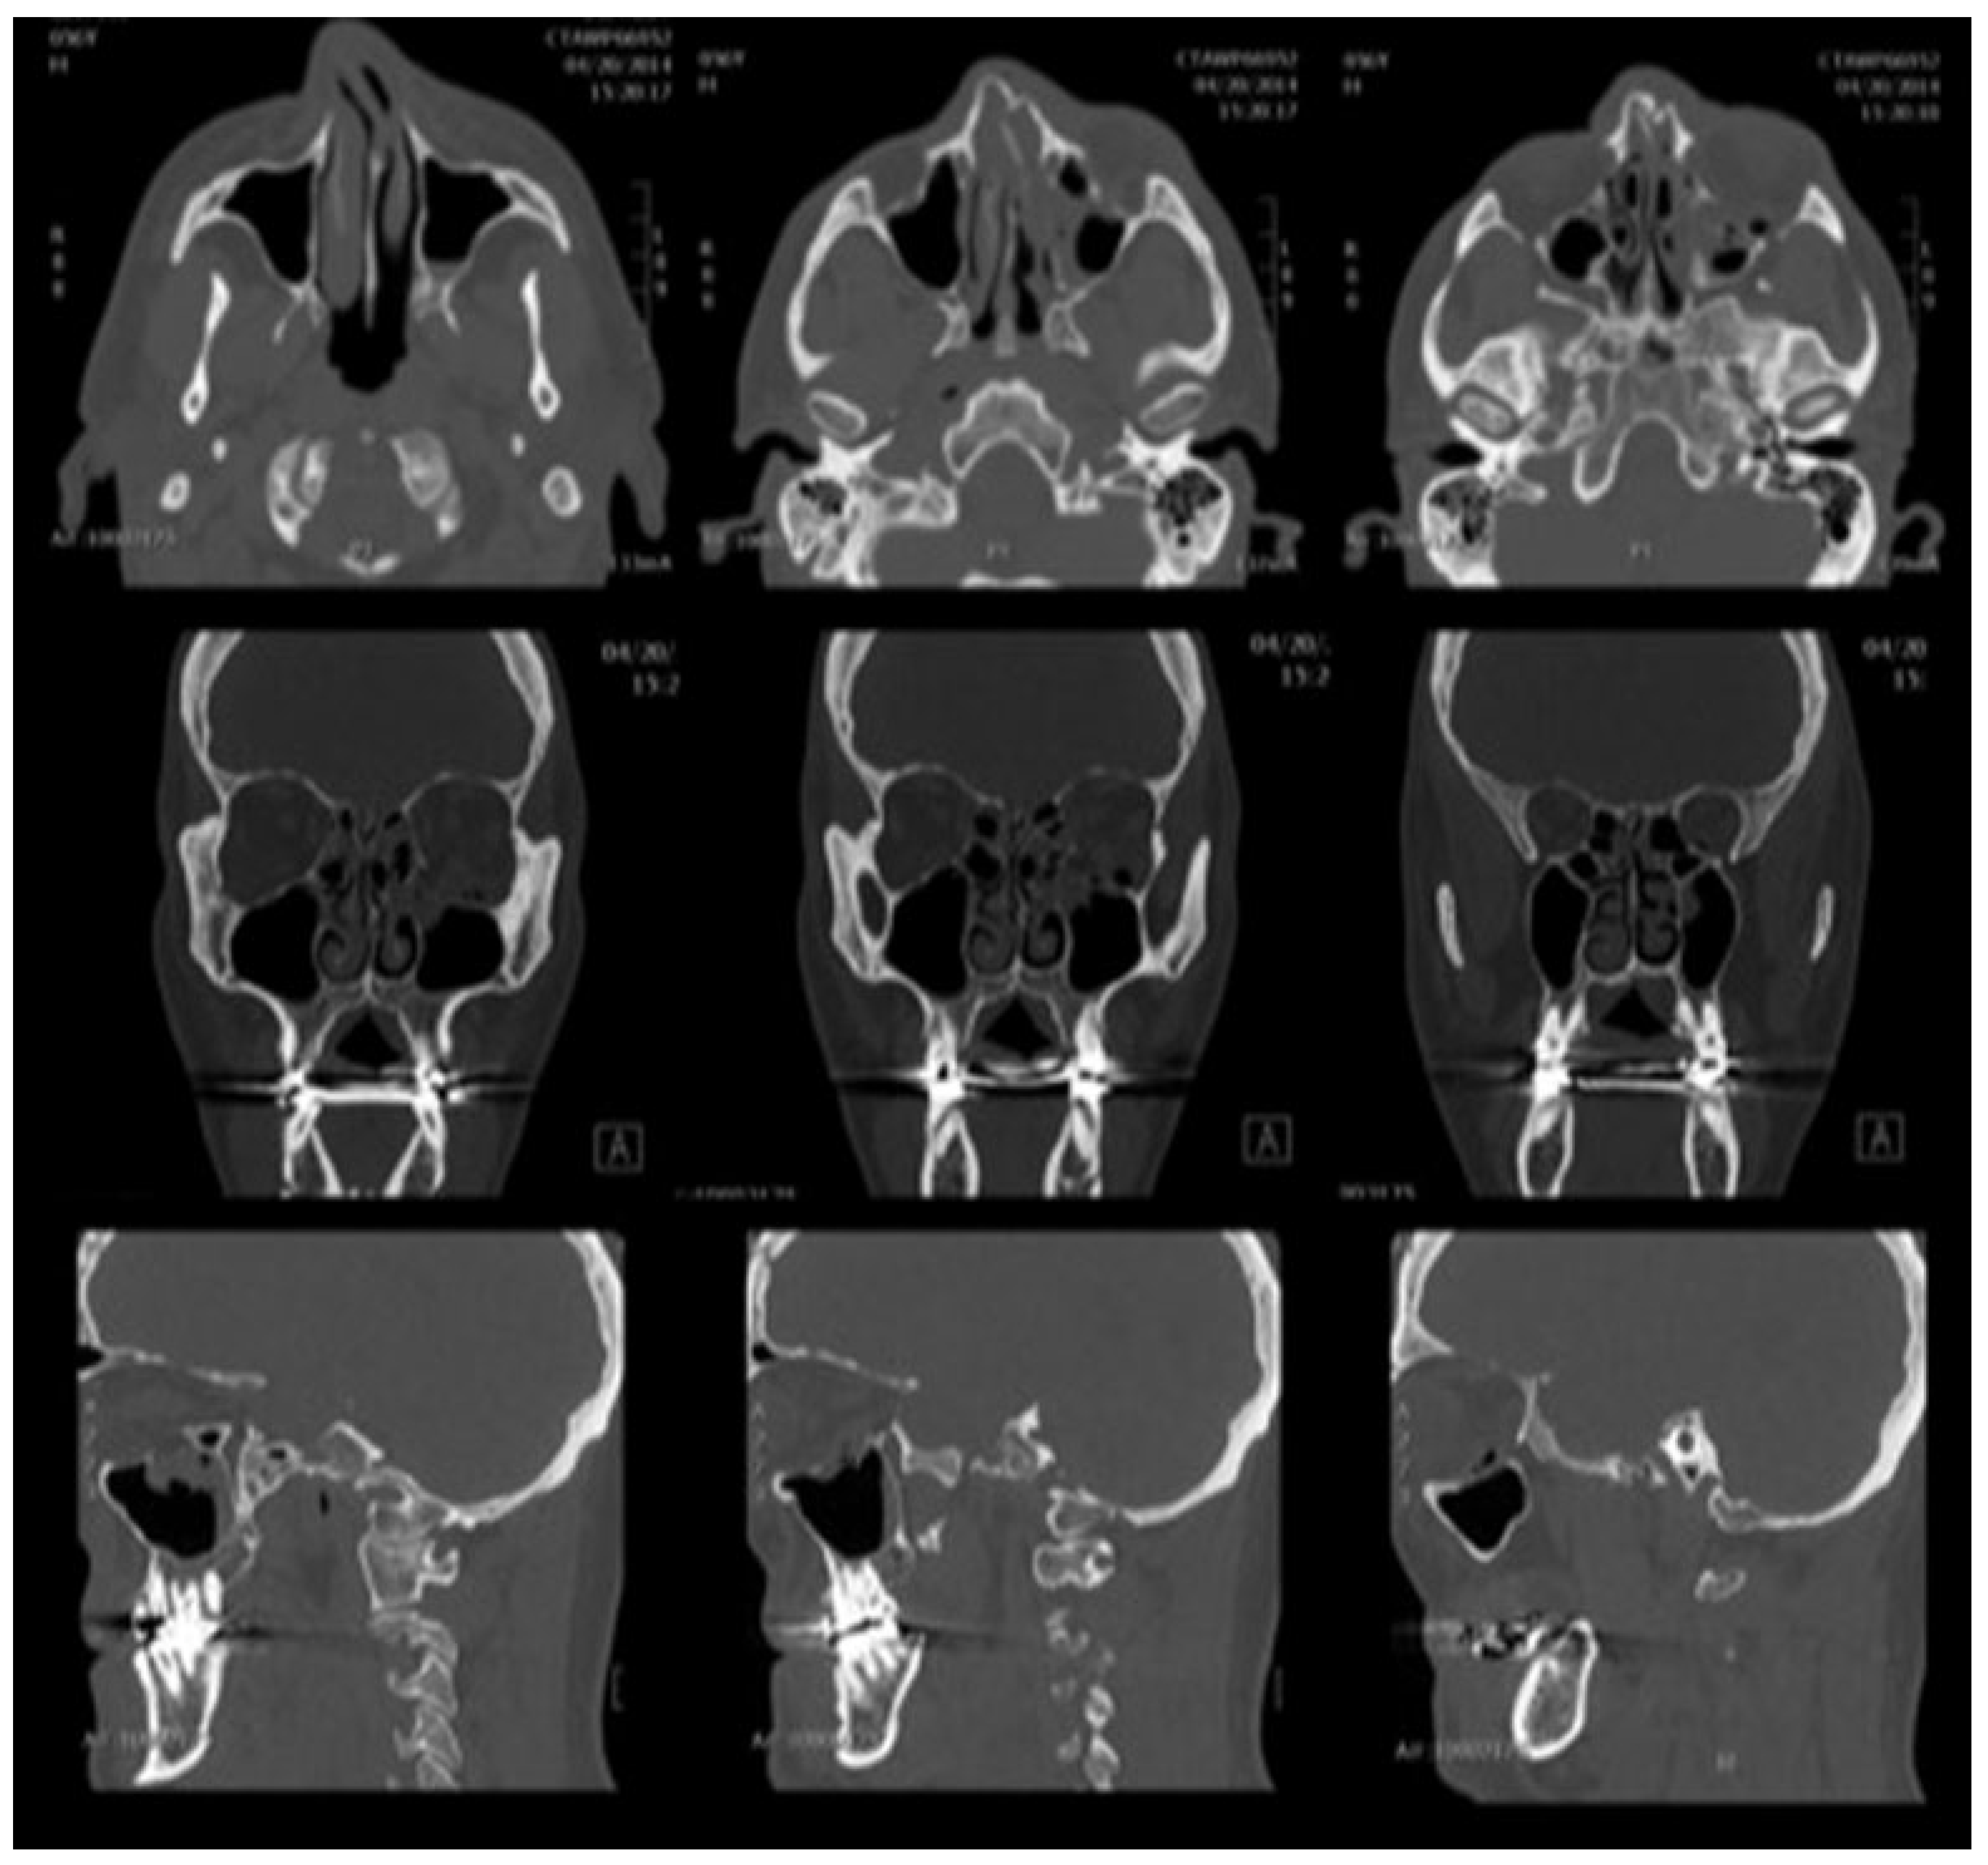

Maxillofacial computed tomography demonstrated a fracture of the left orbital floor, with herniation of fat into the maxillary antrum and left nasal bone fractures, as well as a deviated nasal septum (Figure 2). There was no evidence of retrobulbar hemorrhage, inferior rectus entrapment, or fracture into the orbital apex. Routine preoperative laboratory evaluations, including coagulation studies, were unremarkable.

Figure 2. Preoperative computed tomography. Axial (top row), coronal (middle row), and sagittal (bottom row) images show a sizeable orbital floor defect with herniation of soft tissue contents into the maxillary antrum, without evidence of extraocular muscle entrapment, globe injury, or retrobulbar hemorrhage.